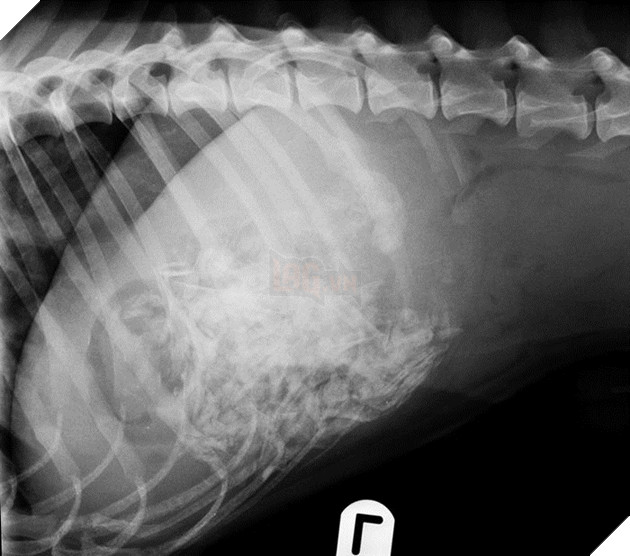

Theo nhận định, có lẽ Shadow đã bị mắc kẹt ở đâu đó trên vách đá nên người ta đã không tìm ra nó. Các bác sĩ phát hiện thấy trong dạ dày của nó chứa đầy sỏi, gỗ vụn, rong biển và nhiều thứ linh tinh khác. Có lẽ nó đã cố gắng duy trì sự sống bằng cách ăn rong biển và uống nước bằng cách liếm vào những hòn đá và những thanh củi ướt trong suốt 45 ngày qua.

Ảnh chụp X-quang cho thấy trong dạ dày nó có rất nhiều thứ linh tinh, từ rong biển khô cho tới gỗ vụn và cả sỏi nữa.